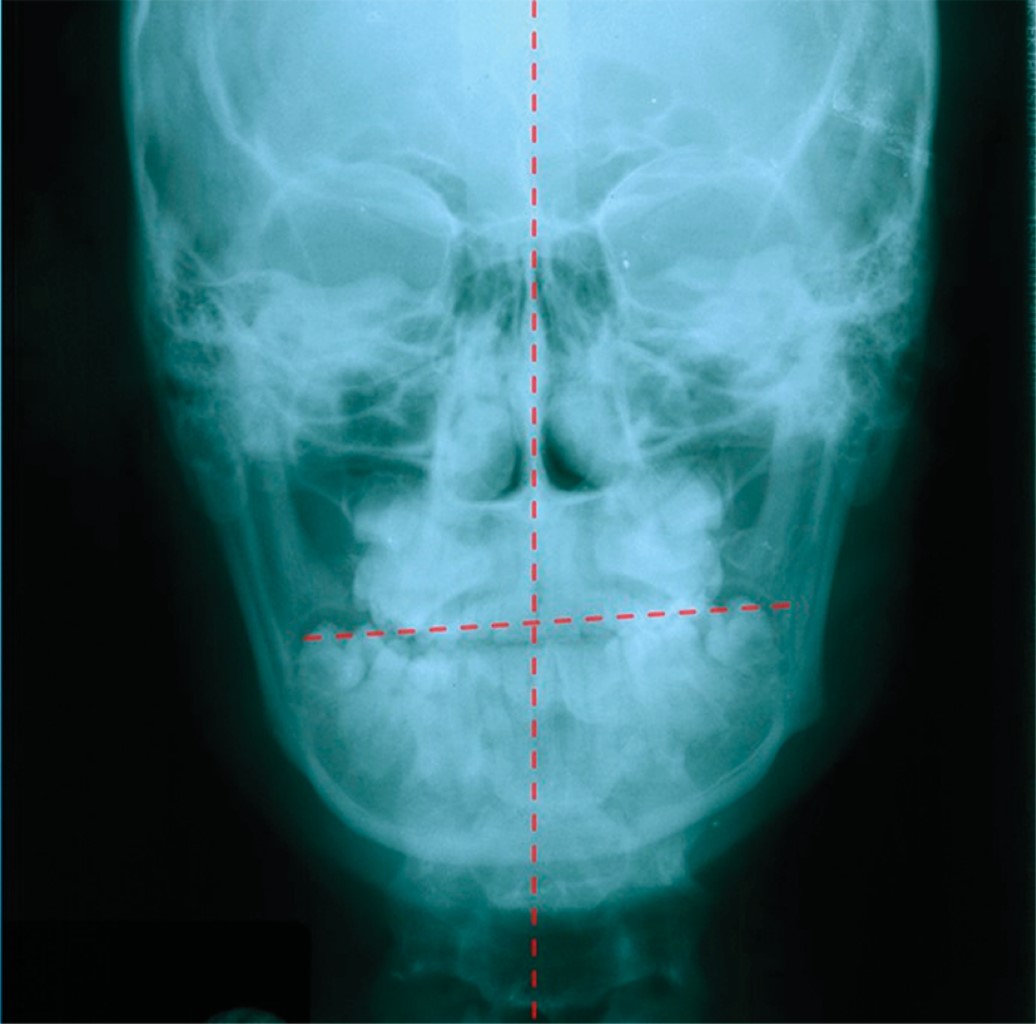

Los planos transversales llegan a sufrir alteraciones no nada más dentales, sino también dentoesqueletales que pueden ser alteraciones congénitas o del desarrollo.

Las asimetrías estructurales craneomandibulares son de origen congénito (heredofamiliar) o adquirido (traumático y/o infeccioso), que durante el crecimiento se pueden llegar a acentuar dependiendo de la severidad o manifestación de ésta. Las alteraciones repercuten en el asentamiento del plano oclusal y en la mayoría de los casos llegan a producir planos oclusales diferentes, es decir, de un lado se produce un plano oclusal y del lado contralateral otro, dependiendo de la severidad de la asimetría. Las cargas o fuerzas del sistema muscular también son de suma importancia para el desarrollo y correcto funcionamiento de la oclusión porque determinan en gran medida la adaptación o desadaptación del sistema musculoesquelético.17-19

Las asimetrías se presentan en los tres planos del espacio y se pueden llegar a manifestar en los tres tercios de la cara; sin embargo, en el tercio inferior se observa el mayor el problema, quizá porque es donde participan los componentes del sistema estomatognático (músculos, ligamentos, dientes, articulaciones, etc.). El plano oclusal será un factor determinante en la posición y adaptación de la mandíbula, variando los grados de inclinación del mismo o los planos oclusales que presente la oclusión del paciente. Por lo tanto, el grado de inclinación del plano o planos oclusales será directamente proporcional a los grados de desviación de la mandíbula tanto de sus tejidos duros como blandos y con respecto a la línea media facial o elementos de valoración de la simetría facial.11,14,17,18,20

Es frecuente encontrar que en las asimetrías faciales se desarrollen trastornos temporomandibulares (TTM) tanto en el lado hacia donde se presenta la desviación de la mandíbula como hacia donde se encuentra el canteamiento del plano oclusal, donde es más frecuente en el lado ipsilateral (lado hacia donde está el canteamiento), que del lado contralateral. La mayoría de los estudios de asimetría facial se enfocan en la desviación de la mandíbula, y algunos han descrito la relación entre la desviación lateral mandibular y la inclinación del plano oclusal.

Existe una fuerte correlación entre la desviación lateral de la mandíbula y el canteamiento del maxilar superior, que tiende a ser la inclinación hacia donde se desvía la mandíbula. Sin embargo, en algunas ocasiones la mandíbula puede estar desviada hacia un lado y el plano oclusal estar inclinado hacia el lado contralateral.

Por lo general, las áreas de mayor fuerza oclusal y de mayor área de contacto oclusal es en el lado hacia donde se desvía la mandíbula y hacia donde está inclinado el plano oclusal. Cabe destacar que no necesariamente es el lado donde predomina la sintomatología de las articulaciones (Figuras 4 y 5).11,12,18,19,21